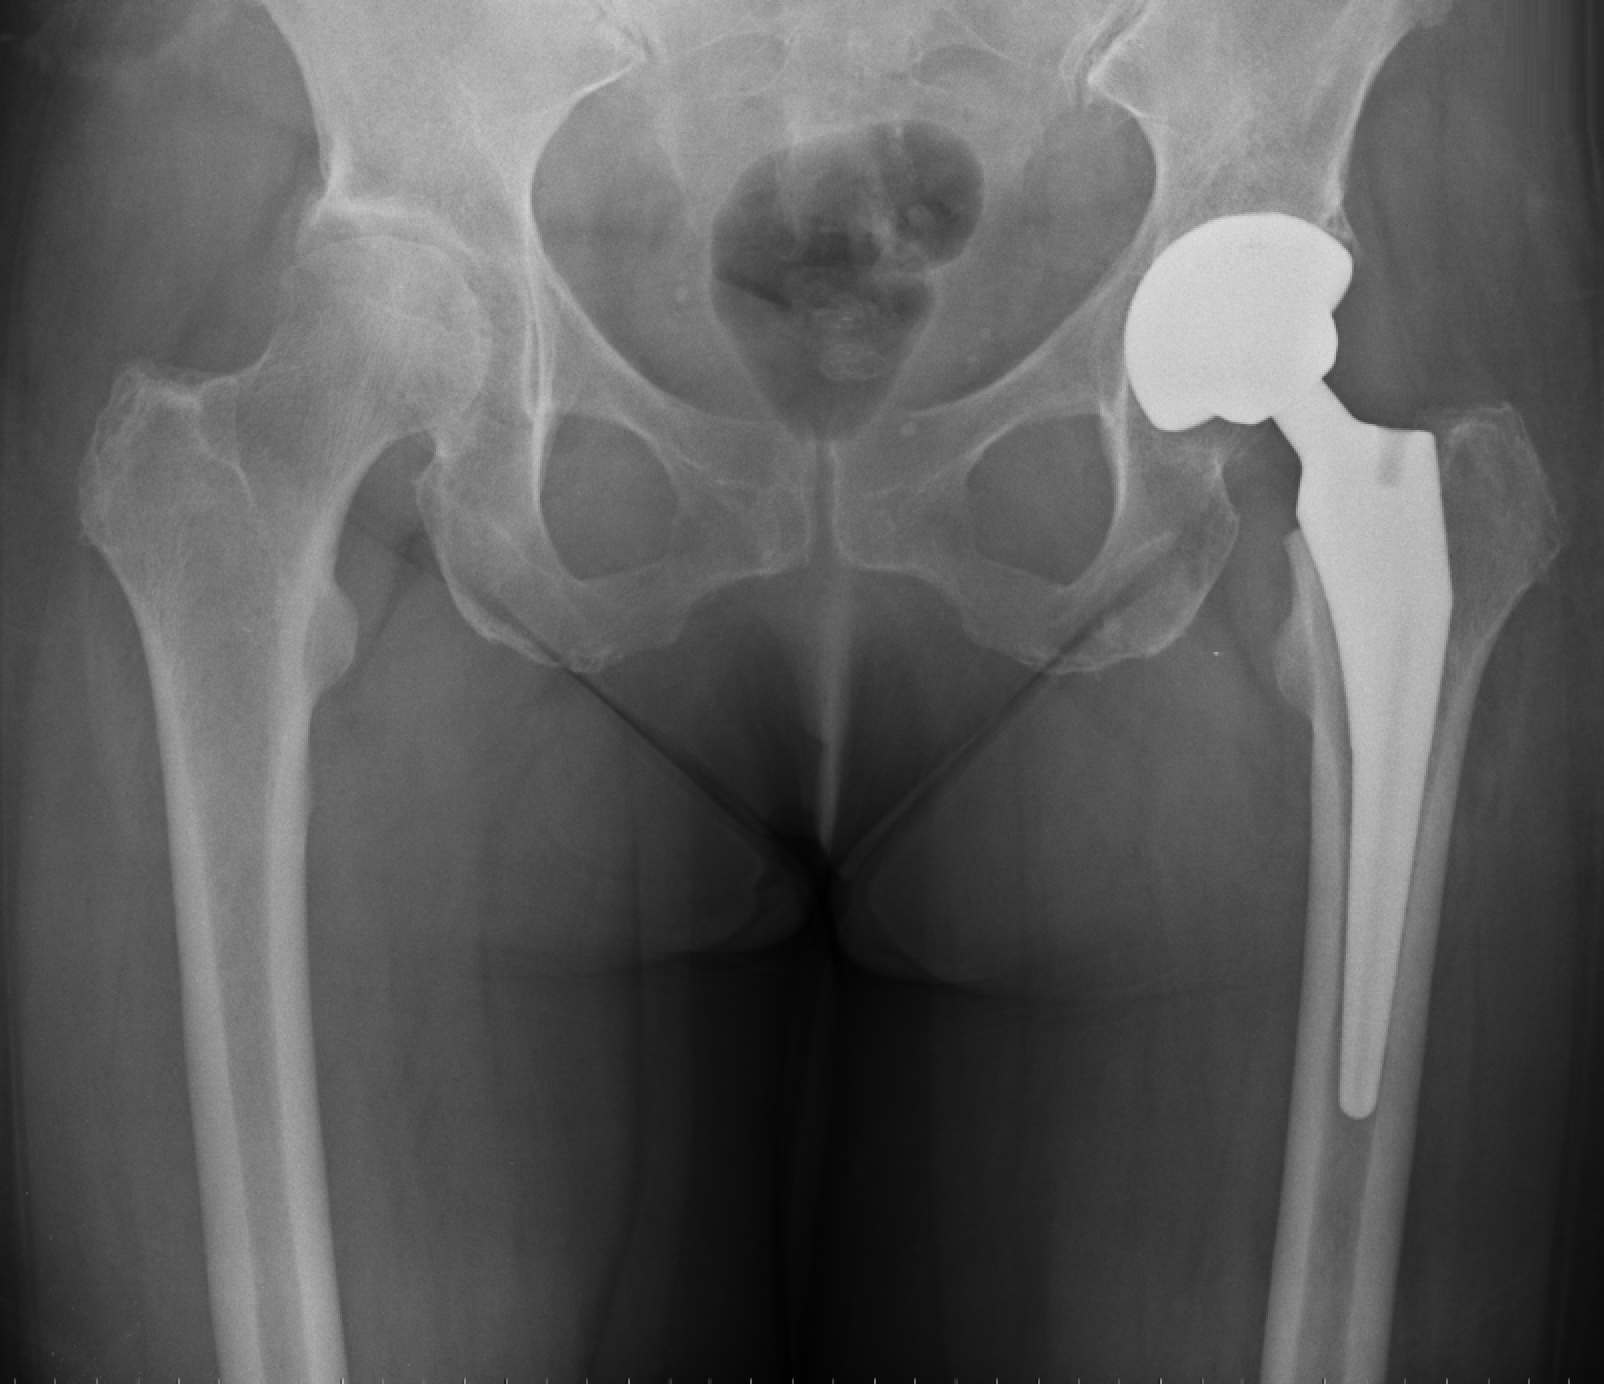

Recognising Hip Arthritis Before It Stops Your LifeHip arthritis is a common cause of pain and stiffness,...